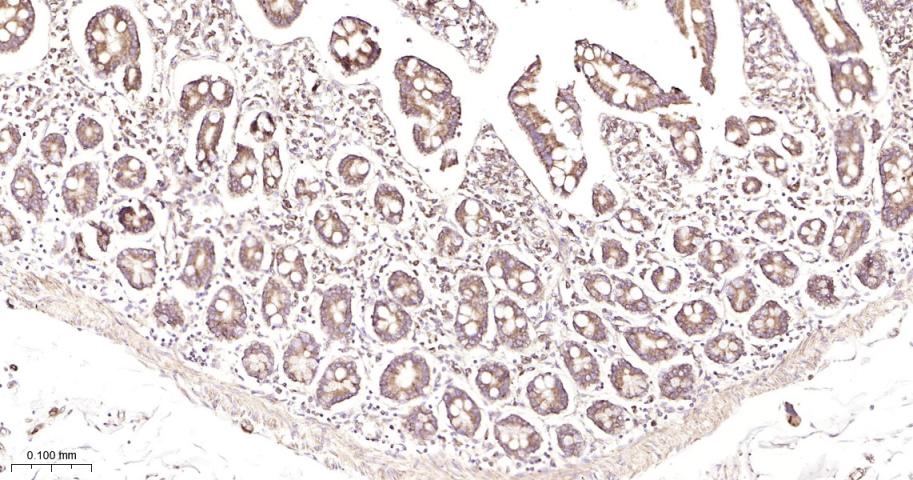

Paraformaldehyde-fixed, paraffin embedded Human Stomach; Antigen retrieval by boiling in sodium citrate buffer (pH6.0) for 15 min; Antibody incubation with PHB1 Monoclonal Antibody, Unconjugated(bsm-61208R) at 1:200 overnight at 4°C, followed by conjugation to the bs-0295G-HRP and DAB (C-0010) staining.